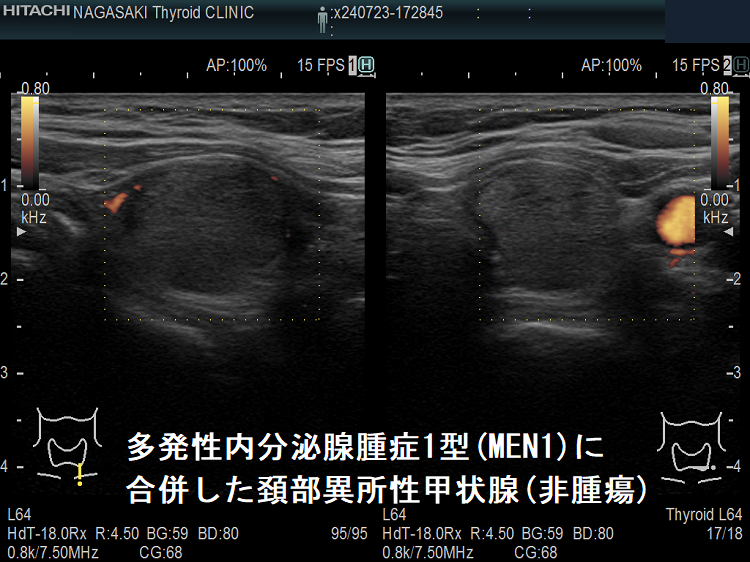

多発性内分泌腺腫症1型(MEN1)に合併した頚部異所性甲状腺(非腫瘍)

多発性内分泌腺腫症1型(MEN1)に合併した頚部異所性甲状腺(非腫瘍);副甲状腺と同じ位置にあるが、内部は甲状腺と同じエコー像

多発性内分泌腺腫症1型(MEN1)に合併した頚部異所性甲状腺(非腫瘍)ドプラーモード

多発性内分泌腺腫症1型(MEN1)に合併した頚部異所性甲状腺(非腫瘍)ドプラーモード;内部血流は乏しく、副甲状腺の血流パターンではない。